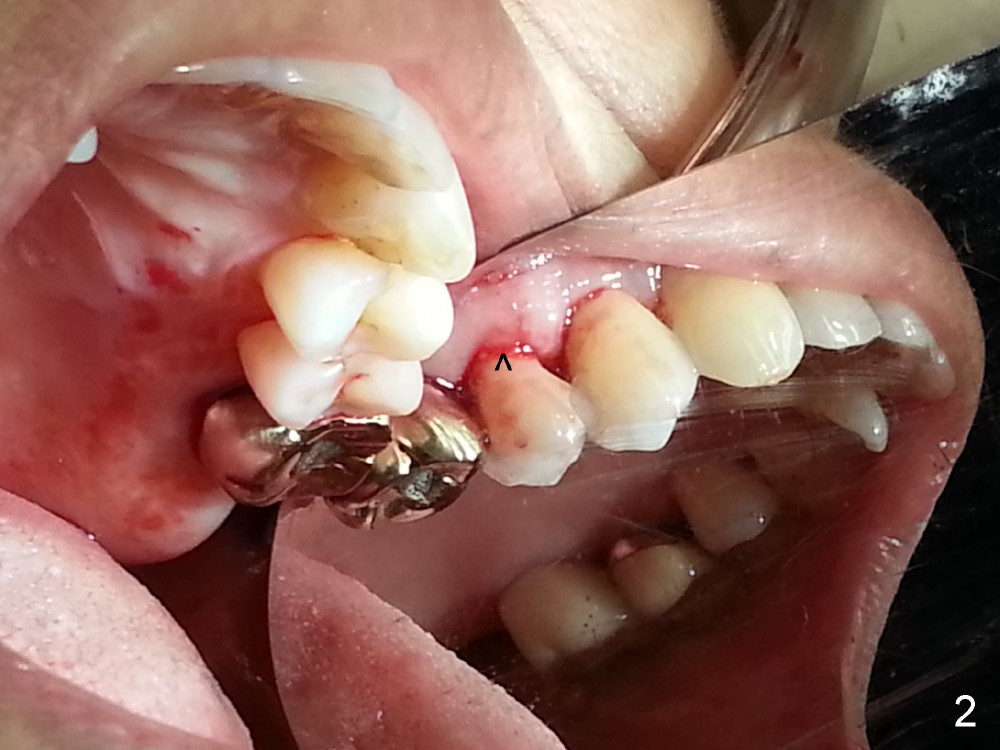

The tooth #13 appears to be affected by periodontits and occlusal trauma (Fig.1*). After using a periotome (Fig.2), the tooth is extracted (Fig.3). The buccal flap is raised (Fig.4). Gingival graft is to be harvested from the site of #15 (Fig.5). The tissue is elevated buccally (Fig.6) and separated (Fig.7). The donor site is covered by a collagen membrane (Fig.8*). A diamond bur is used to induce bleeding from the socket (Fig.9*). Osteotomy is initiated (Fig.10) and enlarged (Fig.11,12). A tapered implant is being placed (Fig.13-15) following internal sinus lift (Fig.16,17). The implant is placed subcrestally, followed by bone graft (Fig.18), soft tissue graft (Fig.19), and suturing (Fig.20 <, Fig.21).